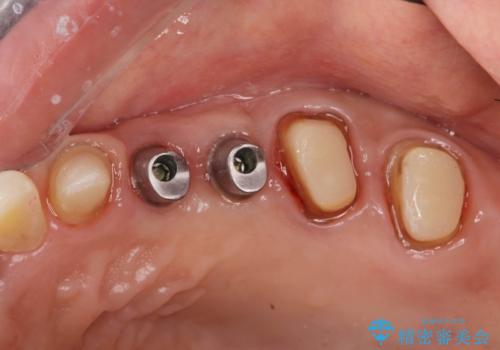

銀歯を除去したところ大臼歯は十分な歯質が残っていたため残すことができましたが、小臼歯の2本は虫歯の再発により残っている歯質が非常に少なく破折リスクが非常に高いと判断しました。

長期的な予後を見込むことが難しいため、相談の上抜去を行いインプラント治療を進めていくこととなりました。

- 123.2万円(インプラント×2・チタンカスタムアバットメント×2・ジルコニアクラウン×4・仮歯×4)費用は治療当時の料金となります